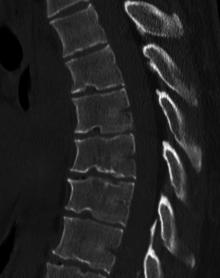

| A 20-year-old male with Scheuermann's disease, showing various measurement of kyphotic/lordotic degrees and their supplementary angles. Notice the signature 'wedging' shape of the four vertebrae in the lower thoracic area. The other vertebral bodies are otherwise normal. The measured kyphosis for this patient is ~70°. | |

Scheuermann's disease is a self-limiting skeletal disorder of childhood. Scheuermann's disease describes a condition where the vertebrae grow unevenly with respect to the sagittal plane; that is, the posterior angle is often greater than the anterior. This uneven growth results in the signature "wedging" shape of the vertebrae, causing kyphosis. It is named after Holger Werfel Scheuermann.[1][2][3]

Diagnosis is typically by medical imaging.